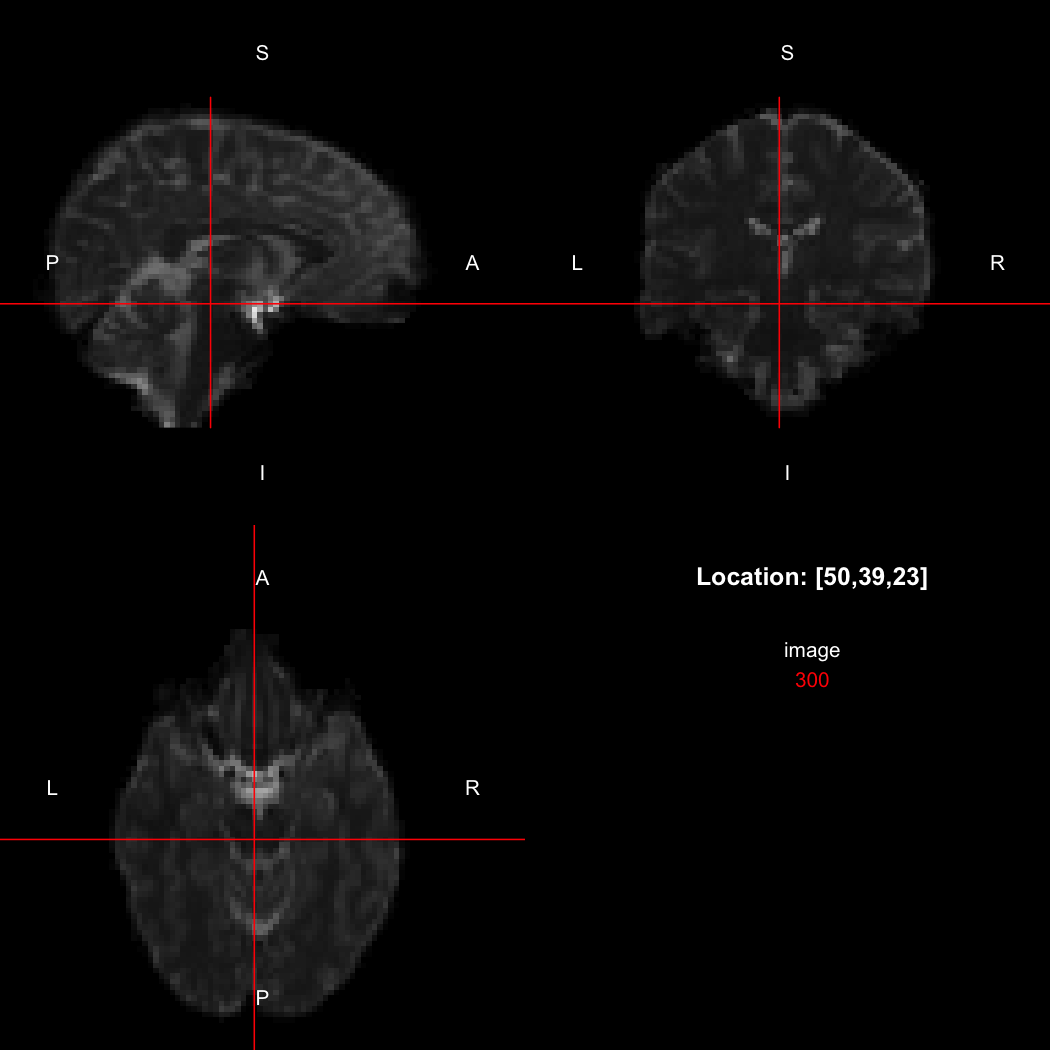

In this case, the image is flipped along the x-axis relative to the canonical axes, so the positive x-direction points towards the left rather than the right. This is compactly represented by the output of the orientation function, which indicates the approximate real-world directions of the positive axes in each dimension.

orientation(image)

## [1] "LAS"

So, here, “LAS” means that the positive x-axis points left, the positive y-axis anterior and the positive z-axis superior. This is the so-called “radiological” orientation convention, and can be requested when viewing images for those who are used to it:

view(image, radiological=TRUE)

plot of chunk unnamed-chunk-12

Notice the left (L) and right (R) labels, relative to the view shown above. Setting the radiologicalView option to TRUE will make this the default for all future views.

There is a replacement version of the orientation function, which will reorient the image to align with the requested directions. This is a relatively complex operation, affecting the xform and the storage order of the data.

image[50,39,23]

## [1] 300

orientation(image) <- "RAS"

## [1] 310

image[47,39,23]

Notice that the sign of the top-left element of the xform has now flipped, and the value of the image at location (50,39,23) has changed because the data has been reordered. The equivalent x-location is now 47, which is the 50th element counting in the other direction (96 - 50 + 1 = 47).